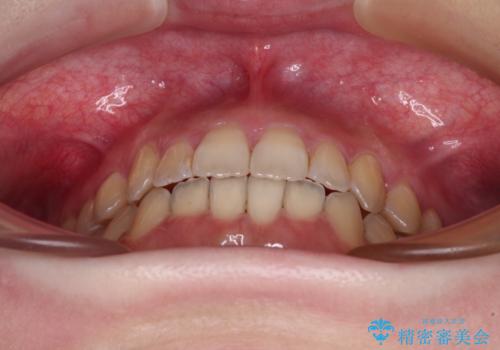

オープンバイトと前歯のデコボコをインビザライン矯正で解消

オープンバイトは舌の突出癖により誘発され、治療後も突出癖が残っている容易に後戻りしてしまいます。

治療期間を短縮するためにも、舌突出癖の改善が極めて重要となります。